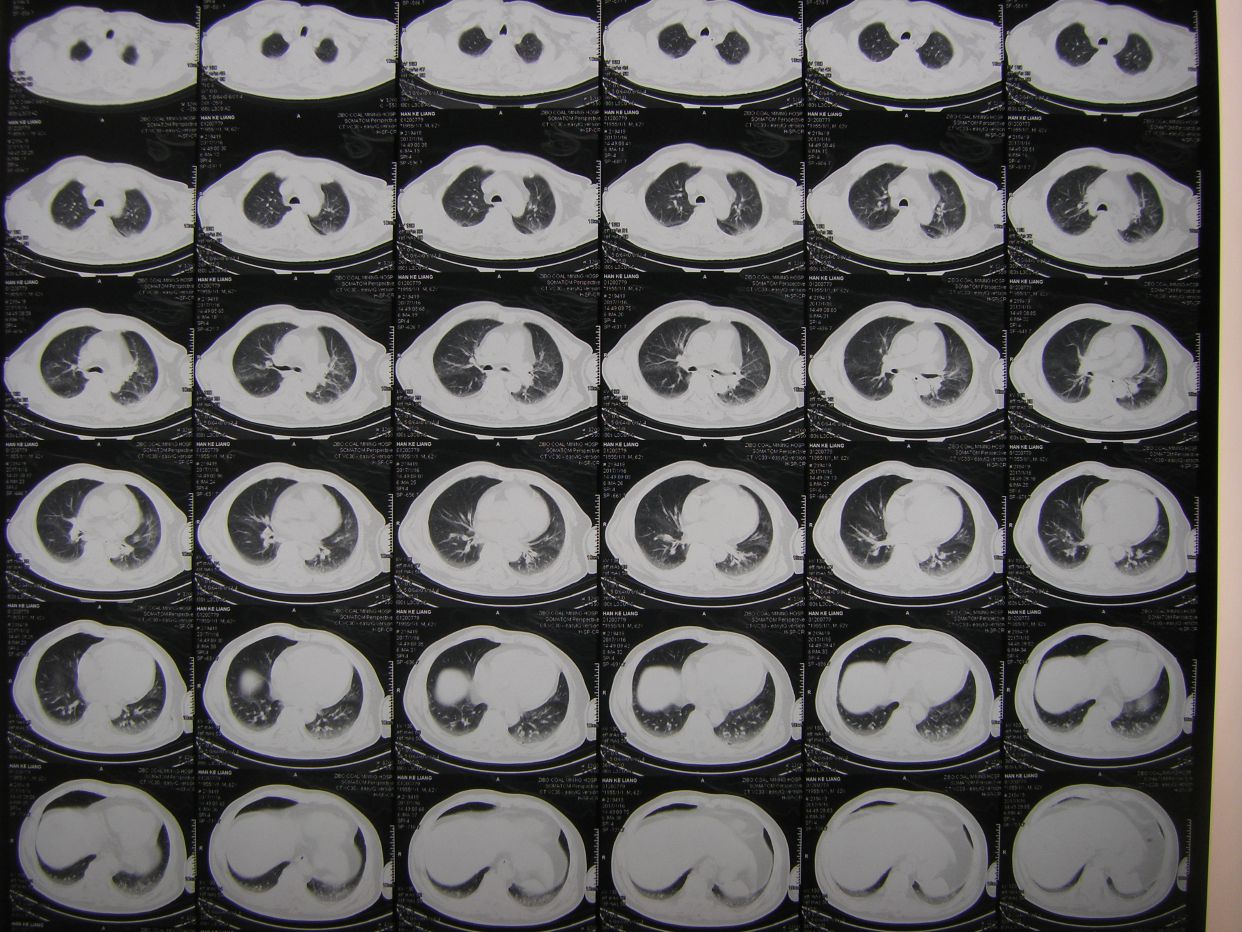

因呼吸急促,氧饱和度低,行胸部CT检查示,双肺野弥漫性斑片状阴影,保留气管插管,拍背吸痰,加强供氧,应用抗炎平喘化痰等药物治疗。

查血气分析示,丨型呼吸衰竭并呼碱,给予呼吸机辅助呼吸。

术后半月胸部CT复查示,肺部阴影消退。患者体温血象正常,神志清,遵嘱动作,右侧肢体肌力3级,出院康复。